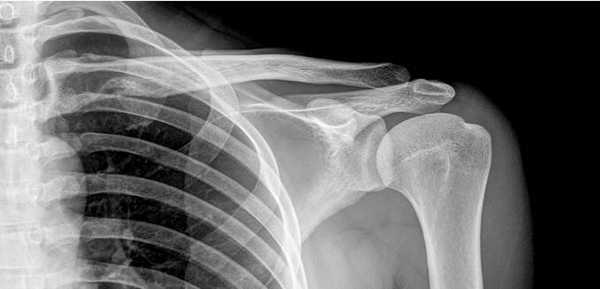

Рентгенограмма плечевого сустава

Рентгенографию осуществляют с помощью ионизирующих потоков, которые проходят сквозь тело человека. Ткани организма обладают свойством поглощать излучение с интенсивностью, зависящей от плотности структур. В результате использования рентгена врач получает черно-белые изображения. Плотные ткани на снимках светлее, чем рыхлые.